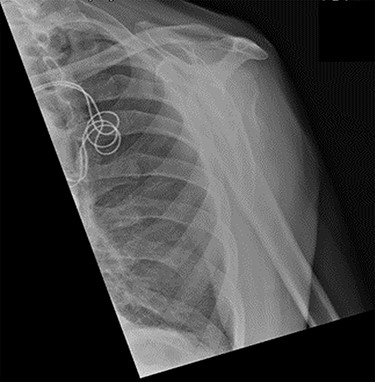

Examination and imaging of the patient revealed that during the fall, he had sustained a left surgical neck of humerus fracture (Fig. 1). Significant skin puckering was noted on the anterior aspect of the left shoulder over the fracture site, otherwise the arm was neurovascularly intact (Fig. 2). He was immediately reviewed by the orthopaedic team who offered surgical fixation of the fracture on the following morning, which was dependent on an appropriate anaesthetic assessment. The patient was in agreement and consented to proceed.

Antero-posterior view X-ray taken on day of admission, showing a left surgical neck of humerus fracture with anterior displacement of the proximal humeral shaft.